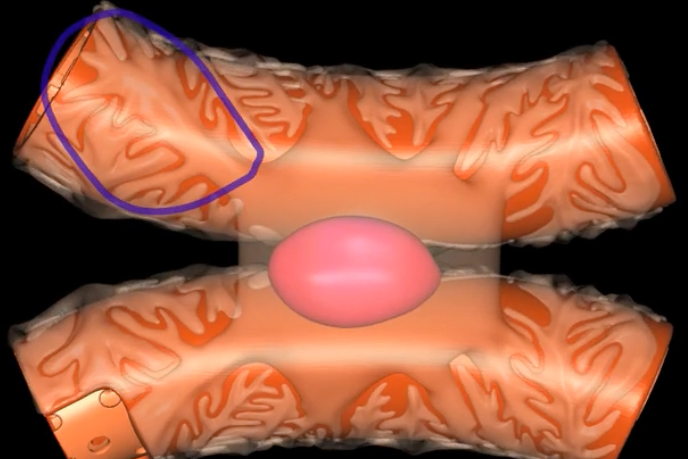

name: proximal convoluted tubule

function: tubular reabsorption

lining: simple cuboidal epithelium w/ microvilli for increased surface area

loop of Henle

red: descending limb

blue: ascending limb

reabsorb ions

blue’s function

reabsorb water

red’s function

green: thick segment lined with simple cuboidal

purple: thin segment lined with simple squamous

name: distal convoluted tubule

function: secretion of H+ and K+ ions

lining: simple cuboidal, sparse microvilli